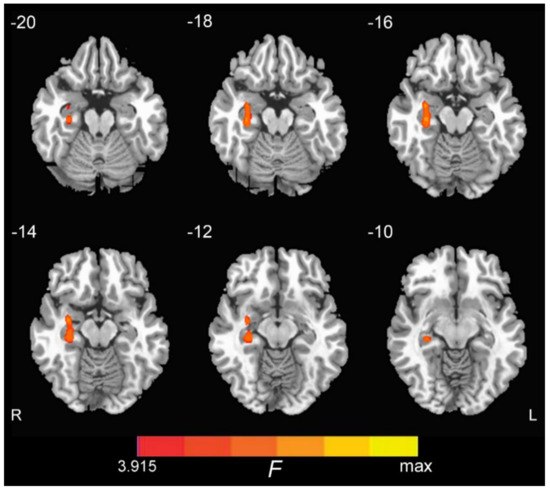

3.2. ON FC Differences and the Region of Interest (ROI) Analysis

| Cluster | Cluster Size (Voxel) | MNI Coordinates | t Value | ||

|---|---|---|---|---|---|

| x | y | z | |||

| Right Hippocampus | 74 | 33 | −6 | −15 | 7.59 |